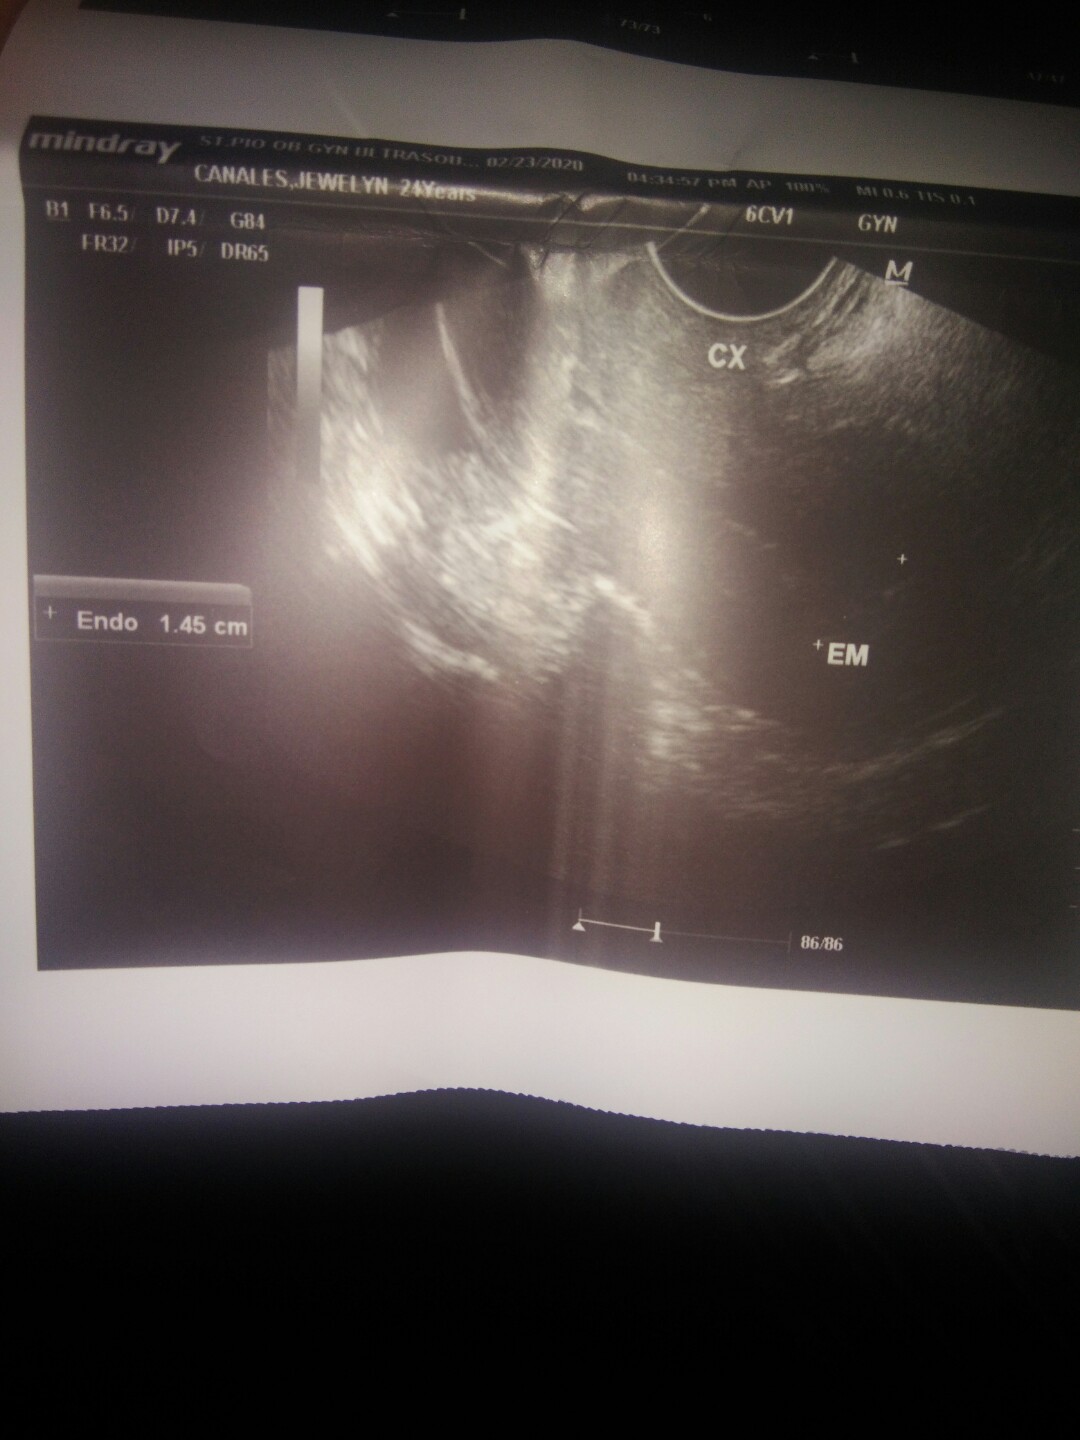

7weeks and 5 days po ako ngayon, nagpa transviginal ultrasound po ako at sabi ng OB ay wala daw cyang makitang baby..?hindi daw ako buntis.. ? pero nag pt po ako kaninang umaga bago ako pumunta positive naman.. Bat. Ganun.. Lahat ng pt ko positive nman.. ???

1.45 cm ano po meaning nun??